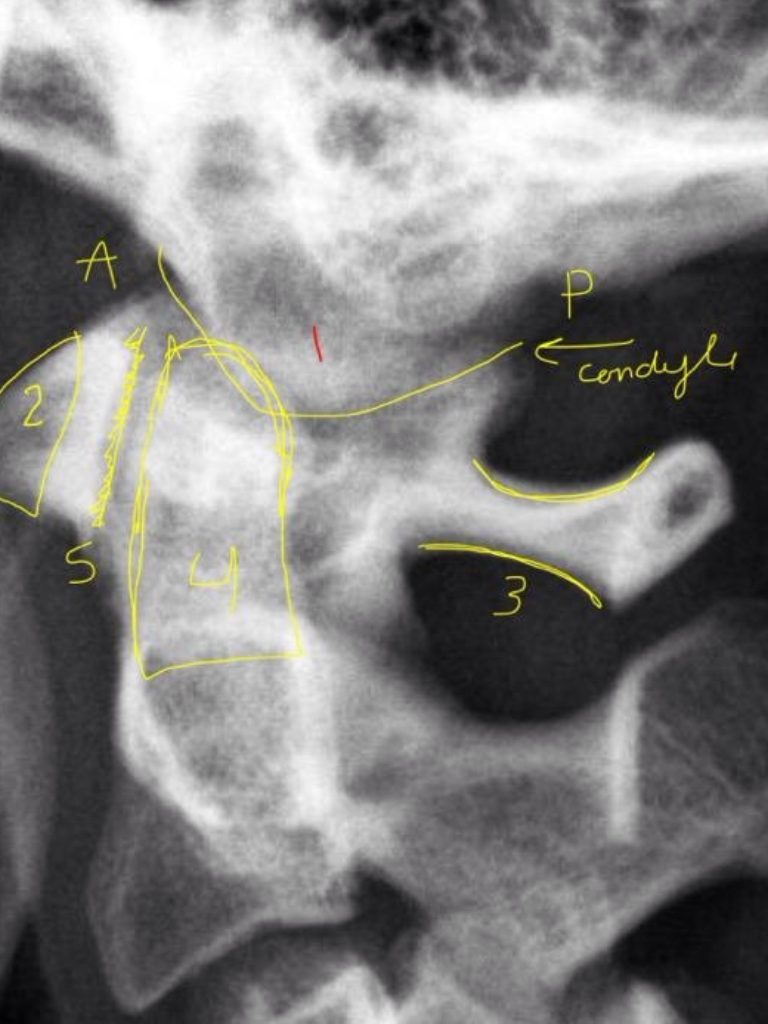

Ocipital Condyles

Foramen Magnum

Lateral Masses of C1

C1 TVP/Lateral Mass Junction

Odontoid Process

C2 Spinous Process

C2 Pedicle shadow

Occipital Condyle

(anterior/posterior)

Anterior Tubercle C1

Posterior Arch C1

Odontoid Process C2

Atlanto-Dental Interspace